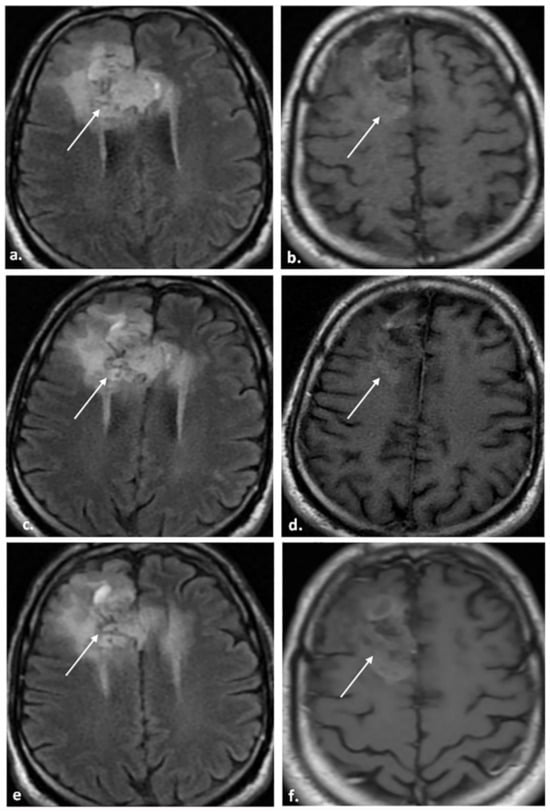

| BT-RADS-3a | Worsening may represent the treatment effect. Clinically stable. | Mild increase (<25%) in enhancing component, FLAIR component, or mass effect compared with prior MRI. | Decreased time interval of follow-up. |

| BT-RADS-3b | Indeterminate. Worsening may be a mix of TP and treatment effects. Clinically stable. | Moderate increase in enhancing component, FLAIR component, mass effect, or new lesion compared with prior MRI. | Decreased time interval of follow-up. |

| BT-RADS-3c | Worsening favors TP. Clinically worsening. | Significant increase (>25%) in enhancing component, FLAIR component, mass effect, or definite new lesion compared with prior MRI. | Change in management vs. decreased time interval of follow-up. |